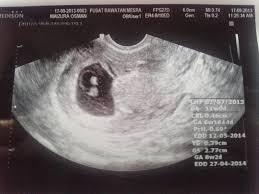

Pengiraan Sebenar Usia Kandungan

Pengiraan sebenar usia kandungan. Cara menghitung usia kehamilan sekiranya wajib diketahui oleh para wanita karena kehamilan adalah salah satu hal yang paling dinantikan ketika pasangan telah mengarungi bahtera rumah tangga. Jom lihat cara mengira usia kandungan di bawah. Tapi cara ni salah dalam mengira usia janin.

Hanya dengan memasukkan beberapa butiran mengenai haid anda kalkulator kehamilan boleh mengira usia kandungan dalam talian. Cara mengira minggu kehamilan biasa kita akan kira 4 minggu mengandung bersamaan 1 bulan pregnant. Kalkulator kehamilan untuk menghitung usia kehamilan dan memperkirakan tanggal kelahiran si kecil yang bisa bunda gunakan kapan saja gratis.

Saat pria dan wanita menikah tujuannya tak hanya untuk menyatukan cinta keduanya tetapi juga untuk mendapatkan keturunan. Cara untuk mengira usia kandungan dengan menggunakan apps dan kalkulator kehamilan dalam talian adalah lebih mudah. Pentingnya pengiraan kehamilan yang tepat bertujuan untuk kira tarikh bersalin.